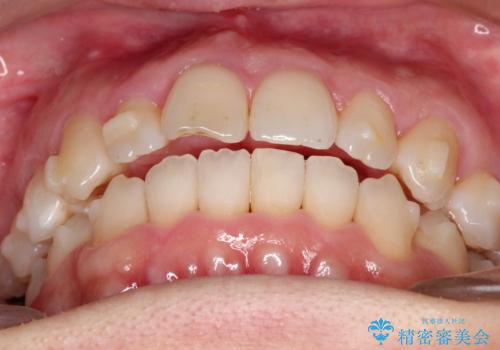

【インビザライン 】前歯のガタガタを治したい

- 前歯のガタガタを主訴に来院されました。

インビザライン で治療しました。途中は使用時間が20時間を切ることもありましたが、それでも頑張って使っていただき1年半で矯正終了することができました。